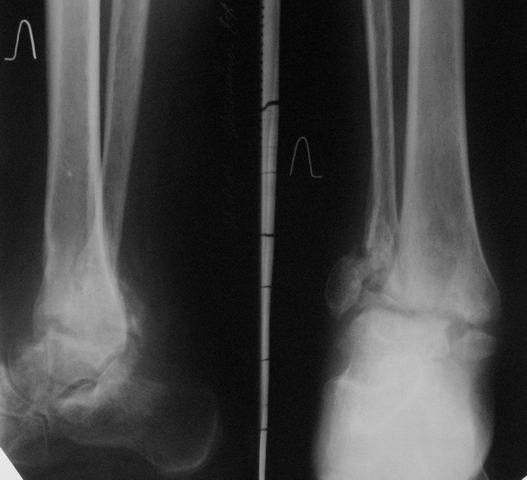

Уважаемые коллеги! Обратилась женщина 45 лет. Травма 2 года назад (март 2005 г.) - открытый 2-х лодыжечный перелом левой голени.

К сожалению, рентгенархив недоступен. Лечилась на вытяжении, затем гипсовой повязкой. Рана у внутренней лодыжки зажила вторичным натяжением. Сращения не наступило. В июне 2005 г. выполнялся артродез по Кэмпбеллу, фиксация в гипсовой повязке 3.5 мес. Сейчас нога полностью неопороспособна, выраженная патологическая подвижность. Признаков инфекции нет. Помогите определиться с методом артродеза, фиксации (КДО?), нужно ли вскрывать сустав, костная пластика? Пациентка, намучавшись за 2 года. "готова на любые эксперименты" (ее слова).Спасибо, с уважением, А. Минервин

Уважаемые коллеги! Спасибо за дискуссию. К сожалению, штифты с блокированием пока недоступны, поэтому рассматриваю вариант с КДО. Все же хотелось уточнить: